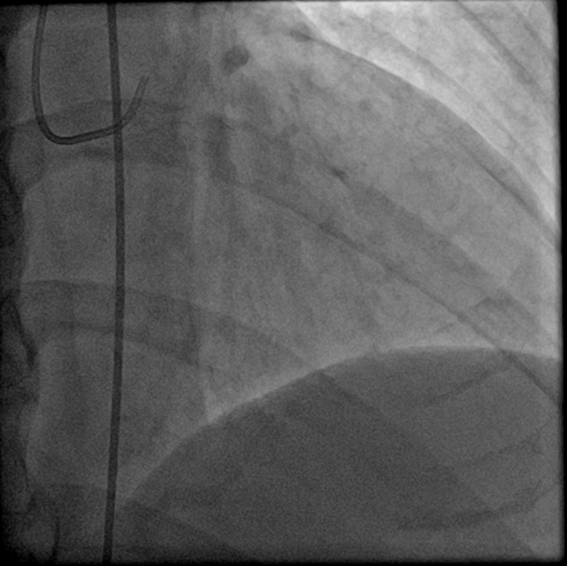

【冠脉造影】

途径:右侧股动脉

术前肝素4000iu

造影结果:LAD中段:100%